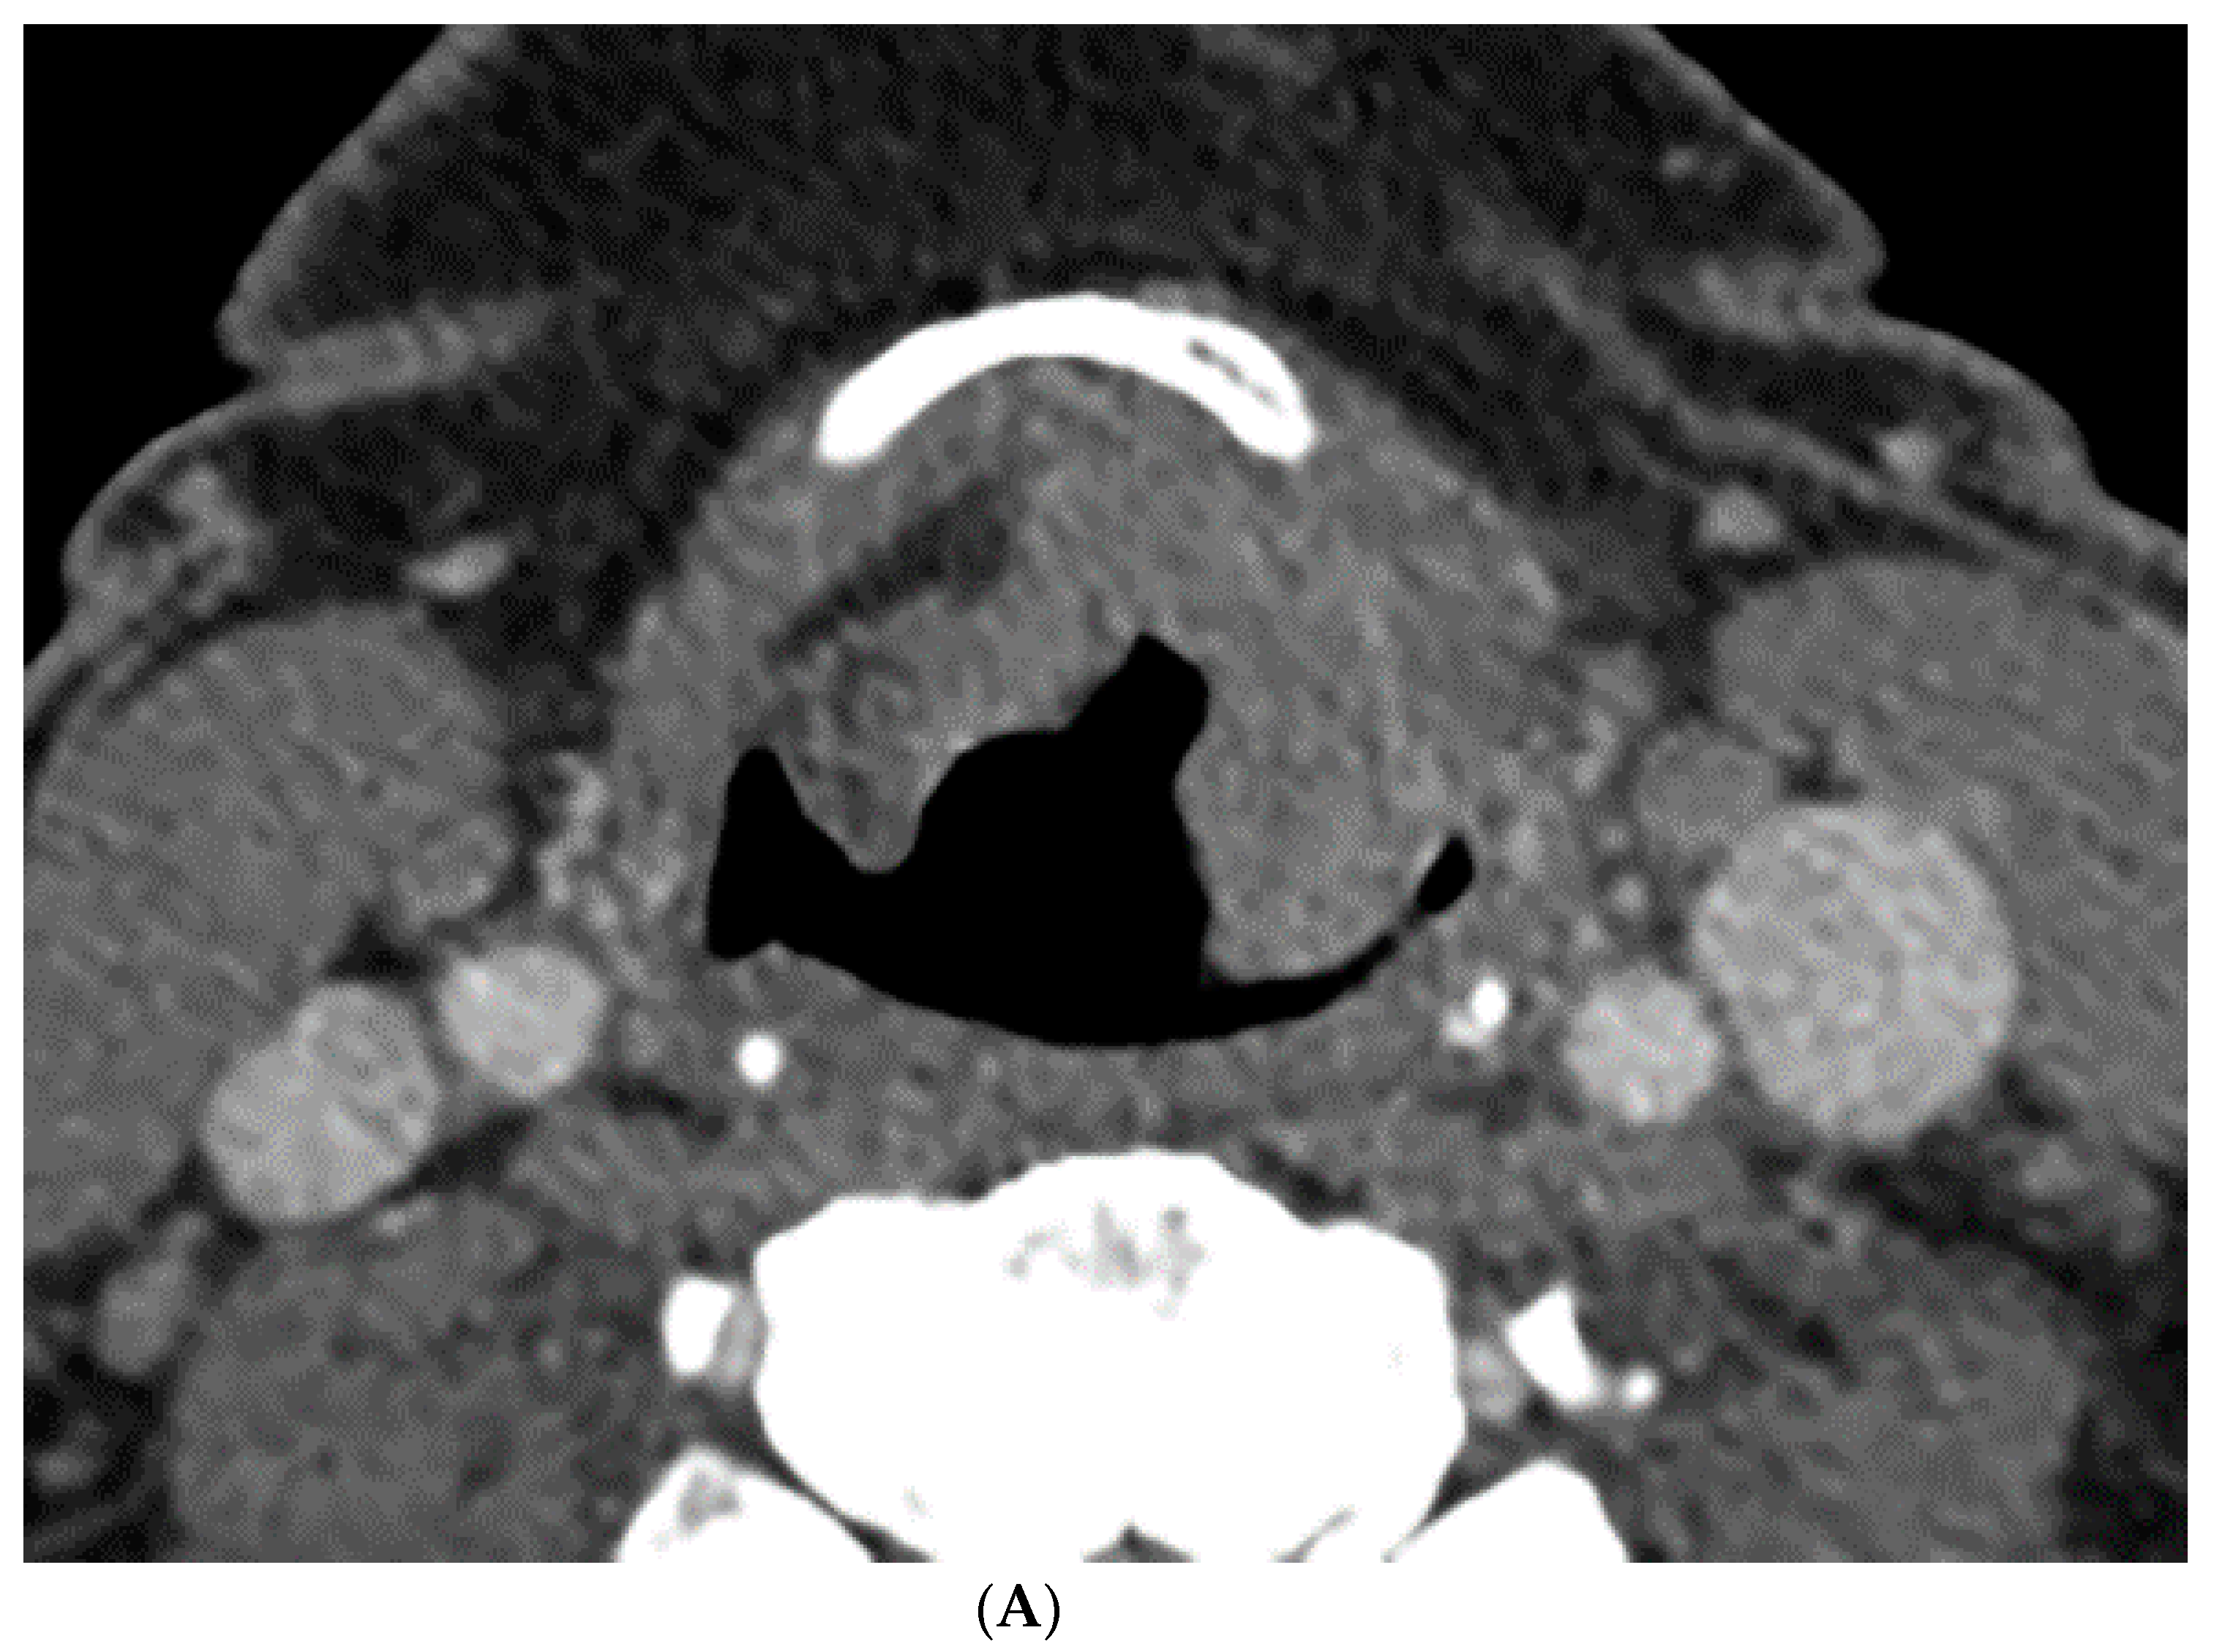

The perfusion data post processing was performed on a commercially available Perfusion-4 software package on an Advantage Windows Workstation version 4.0 (General Electric Medical Systems, Milwaukee, WI, USA). An oval region of interest was placed in the internal carotid artery to generate the contrast arterial enhancement curve. Radiologist 1 (a fellowship trained neuroradiologist with 15 years of experience in head and neck imaging) drew additional freehand regions of interest contouring the tumor along its margin on all axial images where the tumor was visible, and an oval region of interest in normal muscle tissue. An example of the region of interest through the tumor is demonstrated in Figure 1 and Figure 2. The perfusion data were post processed by a deconvolution-based method into maps that represented permeability surface area product (PS), blood flow (BF), blood volume (BV), mean transit time (MTT), and time-to-maximum (Tmax).

Figure 1.

Computer tomography (CT) and perfusion sections of laryngeal carcinoma on pre-treatment images. Axial sections show the grayscale image (A) and outlines for the following: computer (B) and perfusion image (C). Note that the region of interest (ROI) drawn on the CT perfusion image appears different in size from that on the contrast enhanced image; this is because the CT perfusion images are 5 mm in slice thickness whereas the conventional CT images are 1.25 mm in slice thickness (implying that the CT perfusion data is a composite of 4 adjacent 1.25 mm slices from conventional CT).

The percent volume change ICC of the computer with Radiologist 1 or Radiologist 2 were 0.80 and 0.74, respectively. The percent volume change ICC between the two radiologists was 0.73. The differences in the computer-versus-radiologist and radiologist-versus-radiologist ICCs did not achieve statistical significance. Examples of the semi-autonomous computerized 3D level-set segmentation are demonstrated in Figure 1 and Figure 2.